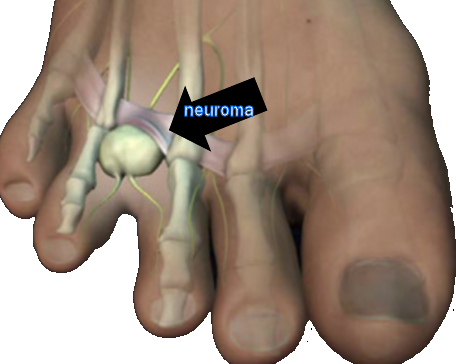

Morton’s Neuroma: A Complete Guide to Symptoms, Diagnosis, and Treatment

Morton’s neuroma is a common cause of forefoot pain. Learn the real symptoms, the tests that matter, when ultrasound helps, the shoe features that reduce pressure, how to place a met pad, and when surgery makes sense.